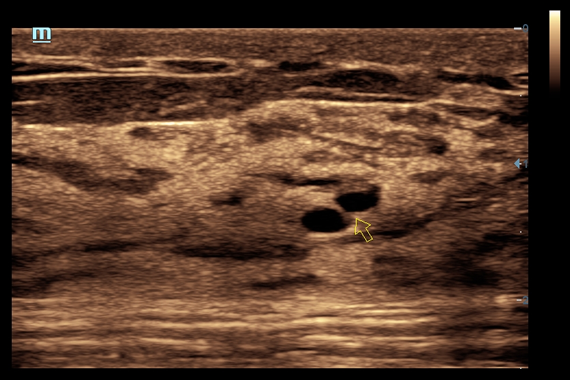

• HR Flow - режим отображения кровотока с высоким временным и пространственным разрешением для точной и однородной визуализации сосудов, в том числе самых мелких.

• iNeedle™ - улучшенная визуализация игл при проведении биопсии линейными датчиками

• Natural Touch Elastography - опция оценки эластичности ткани (эластография), с программой анализа. Действует на линейных датчиках 7L4A, L14-6NE и L9-3E